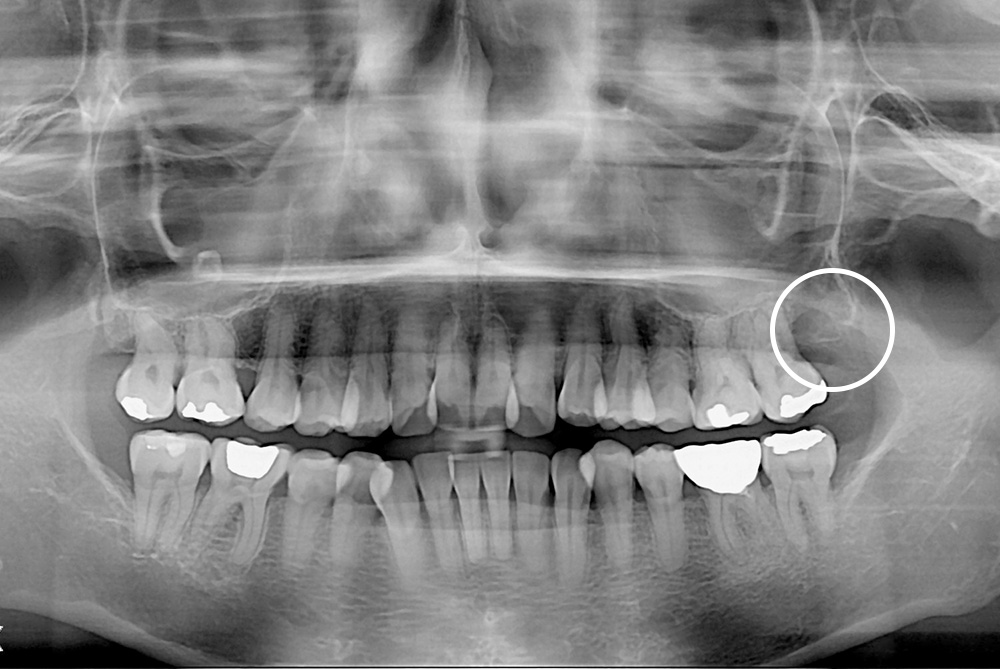

[사랑니] 매복 사랑니 발치

치료후 : 2019-01-17

세종치과는 구강악안면외과학 박사이신 원장님이 발치하는 치과입니다.